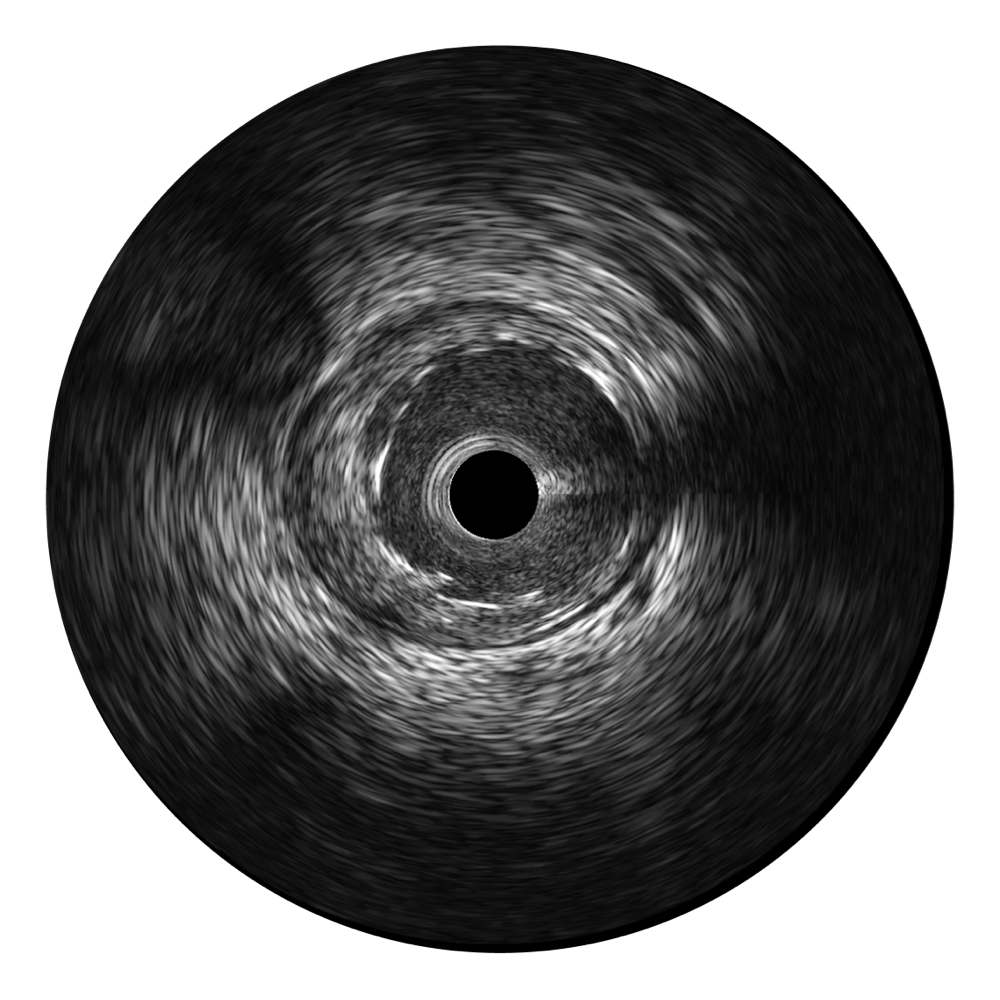

開(kāi)立寬頻IVUS圖像

對(duì)比傳統(tǒng)IVUS導(dǎo)管成像,開(kāi)立寬頻IVUS圖像的近場(chǎng)支架梁顯影更細(xì)膩,遠(yuǎn)場(chǎng)中膜外血管仍清晰可辨,兼顧遠(yuǎn)中近,兼顧分辨力與穿透深度